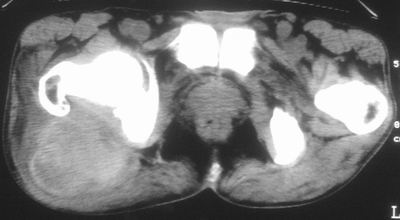

标题: CT16837:M63Y,右臀部巨大软组织包块 [打印本页]

标题: CT16837:M63Y,右臀部巨大软组织包块

患者,男,63岁,自诉3个月前发现右臀部包块,触及疼痛,治疗后缩小。前天突然增大。无高热病史。

考虑-----右臀大肌,臀中肌---感染性病变可能性大。

给个骨窗,判断一下肿块是否与髂骨有关,肿块内出血是肯定的,至于是感染形成的脓肿还是起源于肌肉或纤维组织的肉瘤则难以确定,不过从影像上看,包膜完整,且环形增厚,病灶下部见斑片状底密度坏死,个人倾向感染可能性大

肌间隙明显混浊,三个月前治疗有缩小,支持考虑臀大肌下脓肿伴出血,肿瘤如果出现瘤内出血的话瘤外边界应该较清楚,现在表现为一种恶性征像,但骨质无明显异常,且臀小肌边界清楚,不符合恶性表现.